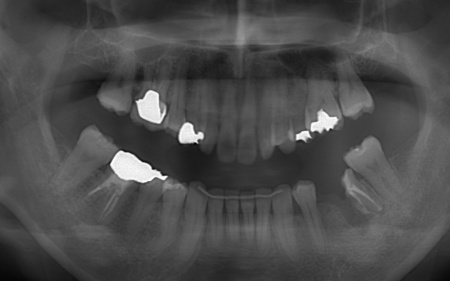

①上あごの骨が狭く歯が並ぶスペースが不足しているため、まず上あごの骨の幅を広げる急速拡大装置を装着する。

成人になってからの骨の拡大は難しいものの、あごの骨に矯正用の小さなネジを埋め、そこを固定源として効率的に歯を動かす治療を併用することでスムーズに拡大を進める。

②①と並行して上下歯列にワイヤー矯正のマルチブラケット装置を装着し、歯並びと噛み合わせを整える。

③矯正治療と並行して左下奥歯を抜歯し、インプラント治療を行う。

インプラントを支えるための骨の量が十分でないため、人工材料を用いて骨を再生させる骨造成(GBR)を併用しながらインプラントを埋入する。